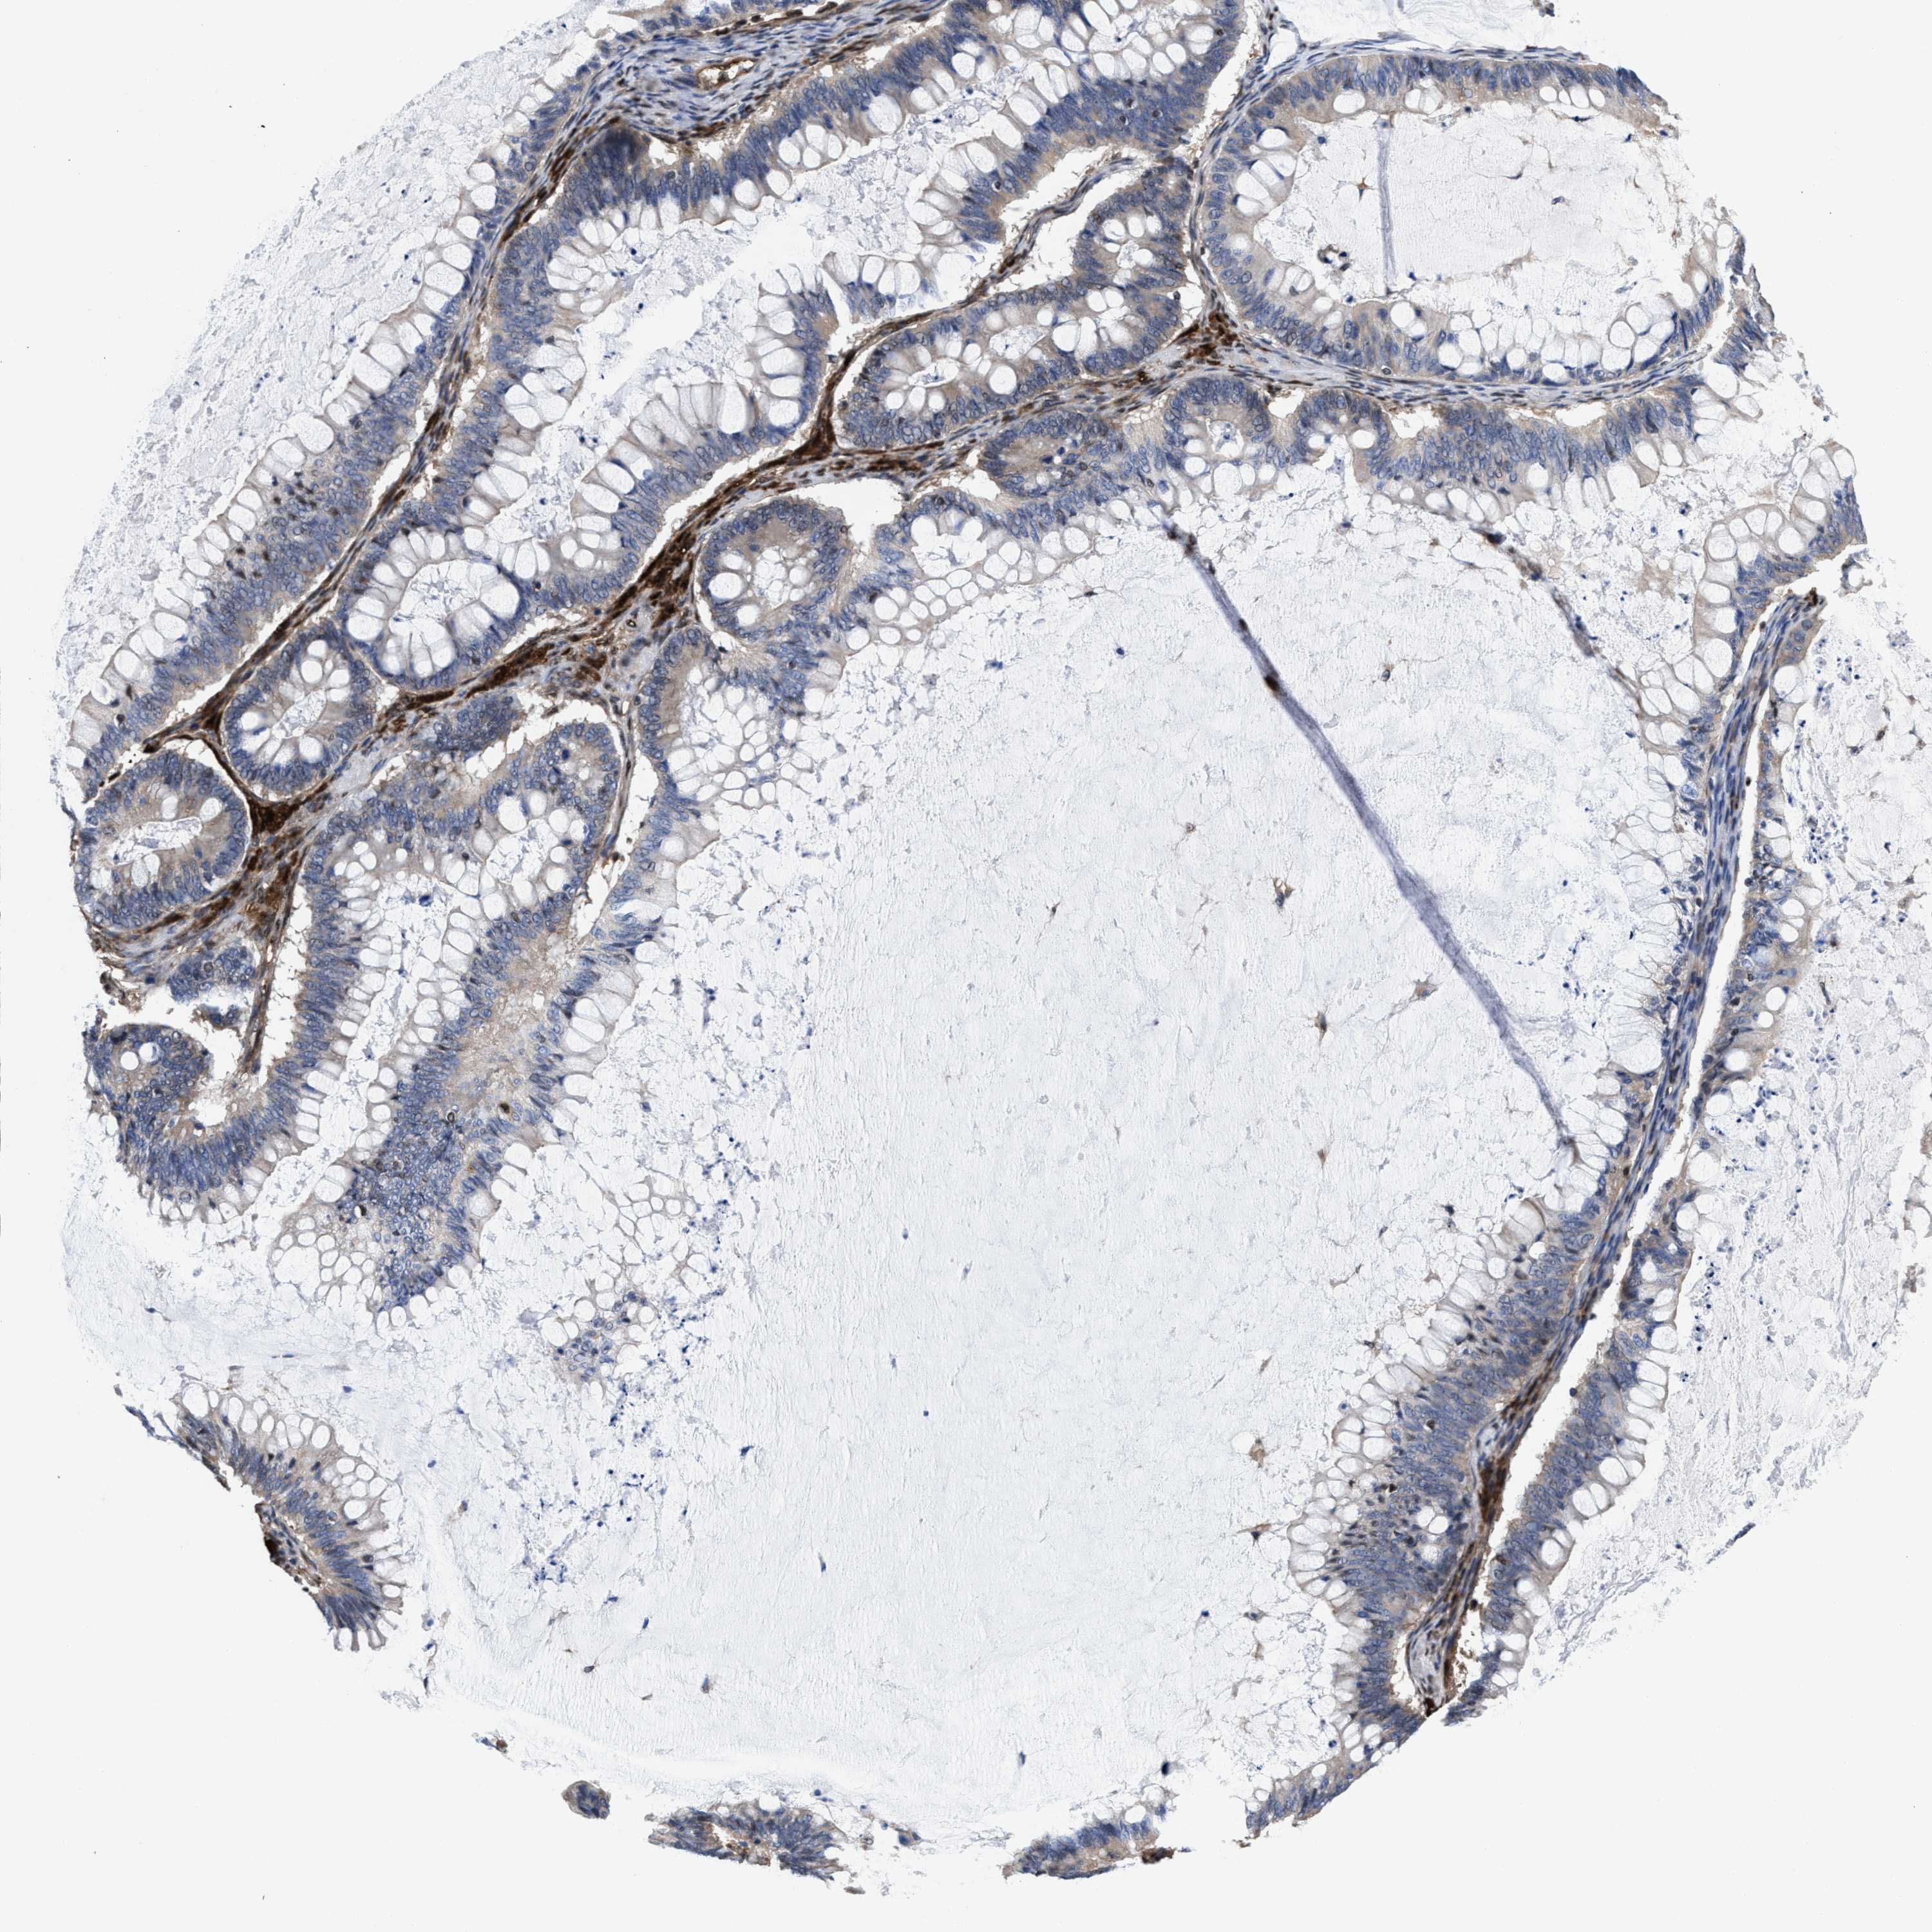

OVARIAN CANCER - Protein expressioni

A mouse-over function shows sample information and annotation data. Click on an image to view it in a full screen mode. Samples can be filtered based on level of antibody staining by selecting one or several of the following categories: high, medium, low and not detected. The assay and annotation is described here.

Note that samples used for immunohistochemistry by the Human Protein Atlas do not correspond to samples in the TCGA dataset.

Antibody stainingi

Antibody staining in the annotated cell types in the current human tissue is reported as not detected, low, medium, or high, based on conventional immunohistochemistry profiling in selected tissues. This score is based on the combination of the staining intensity and fraction of stained cells.

Each image is clickable and will lead to virtual microscopy that enables deeper exploration of all samples and also displays staining intensity scores, fraction scores and subcellular localization as well as patient and tissue information for each sample.

HPA022434

HPA022953

HPA022959

HPA028758

CAB007783

Staining

High

Medium

Low

Not detected

Intensity

Strong

Moderate

Weak

Negative

Quantity

>75%

75%-25%

<25%

None

Location

Nuclear

Cytoplasmic/membranous

Cytoplasmic/membranous,nuclear

Cystadenocarcinoma, serous, NOS

Carcinoma, endometroid

Cystadenocarcinoma, mucinous, NOS

Carcinoma, NOS